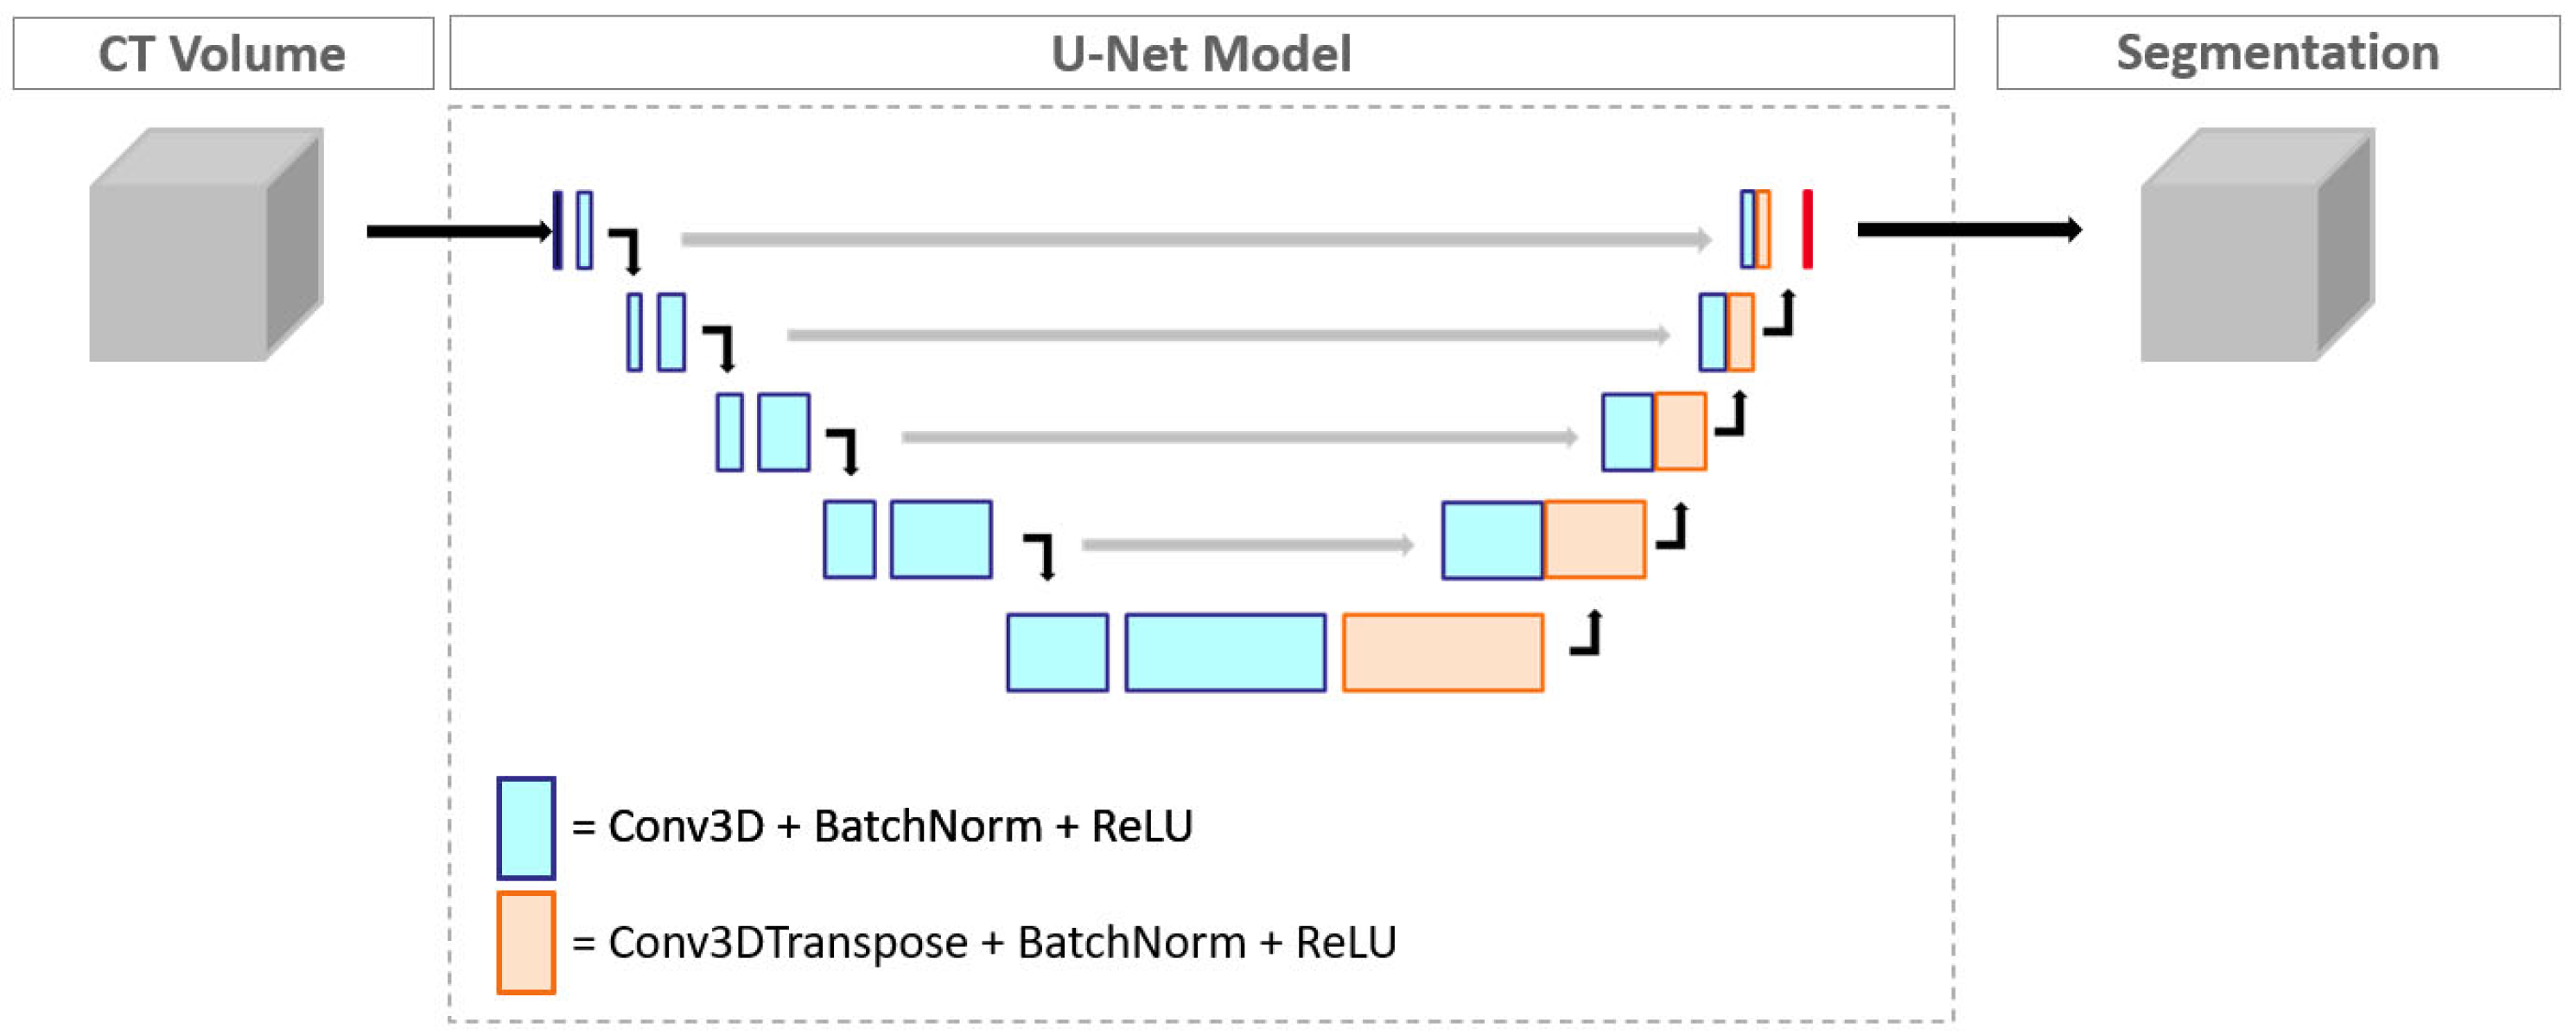

2.3. Convolutional Neural Network Model and Measurements

3.2. Aortic Diameter Quantification in the Entire Cohort

3.3. Subgroup I: Ascending Aorta vs. Descending Aorta

3.4. Subgroup II: Non-Obese vs. Obese Patients

3.5. Subgroup III: Patients without vs. with Prior Aortic Repair

3.6. Subgroup IV: Patients without vs. with Aortic Dissection